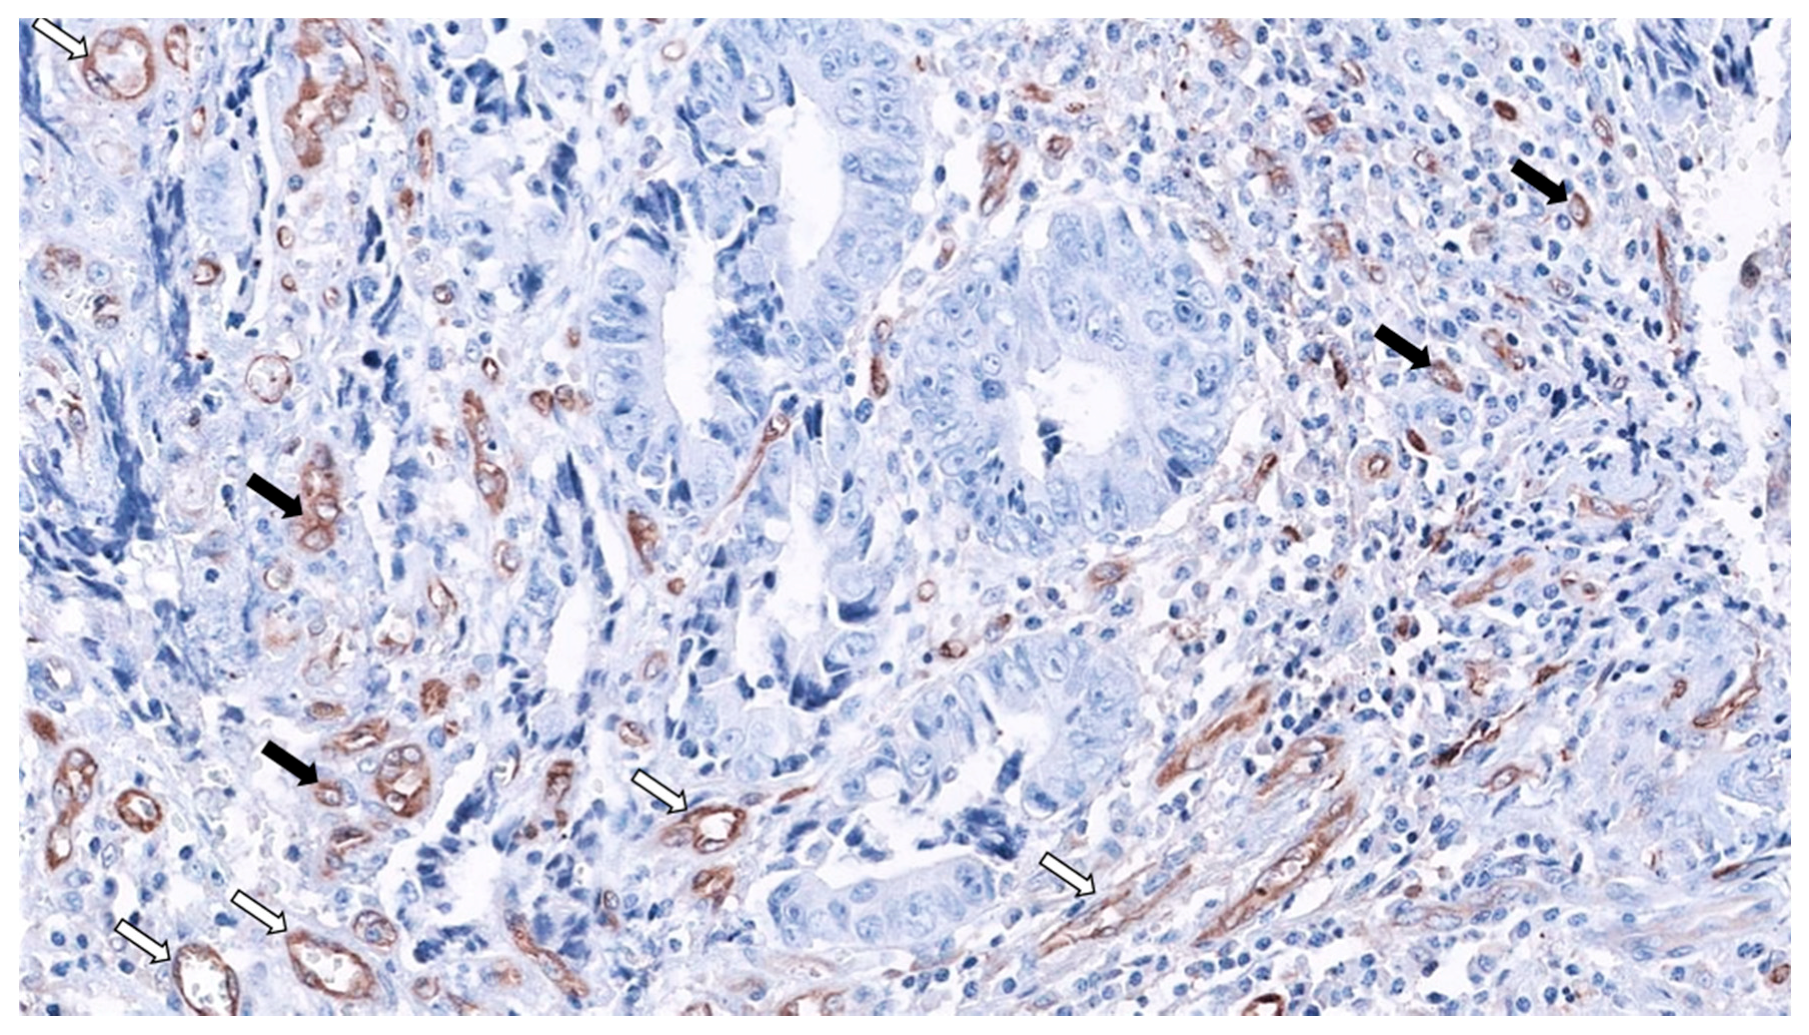

- Tuomisto, A.; García-solano, J.; Sirniö, P.; Väyrynen, J. HIF-1 α expression and high microvessel density are characteristic features in serrated colorectal cancer. Virchows Arch. Int. J. Pathol. 2016, 469, 395–404. [Google Scholar] [CrossRef] [PubMed]